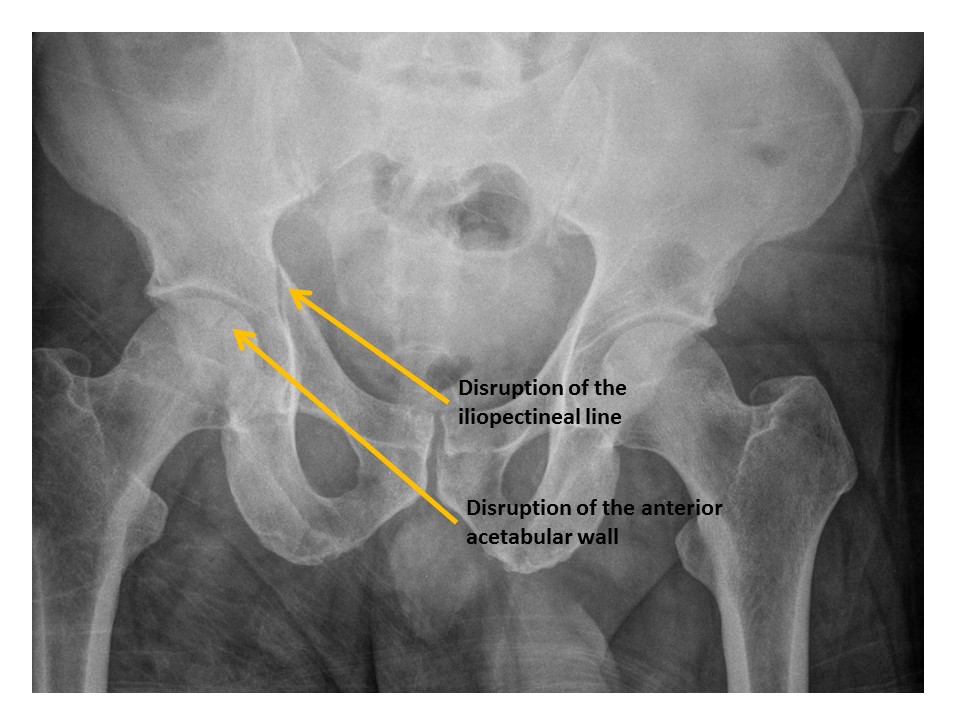

Iliopubic (iliopectineal) lines are disrupted. [Yes/No]

Anterior walls of the acetabula are disrupted. [Yes/No]